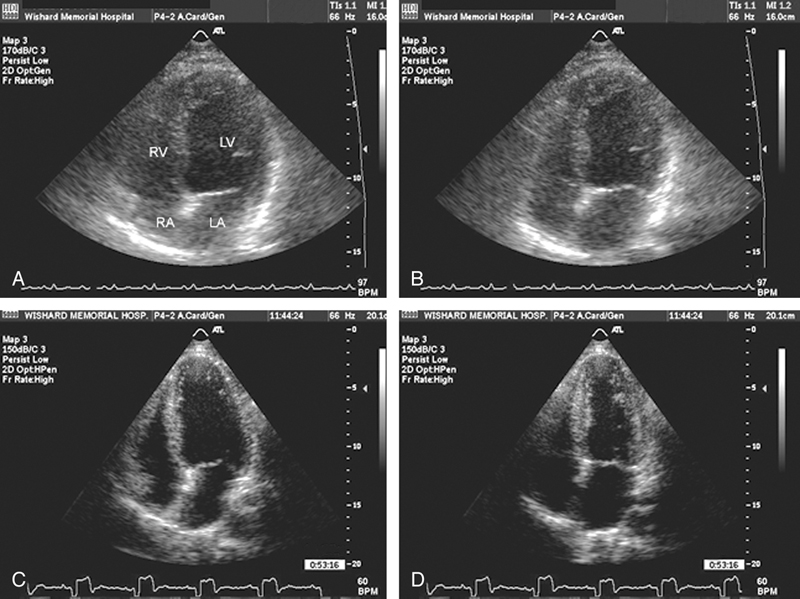

فحوصات تشخيصية لبعض امراض القلب والشرايين التاجية